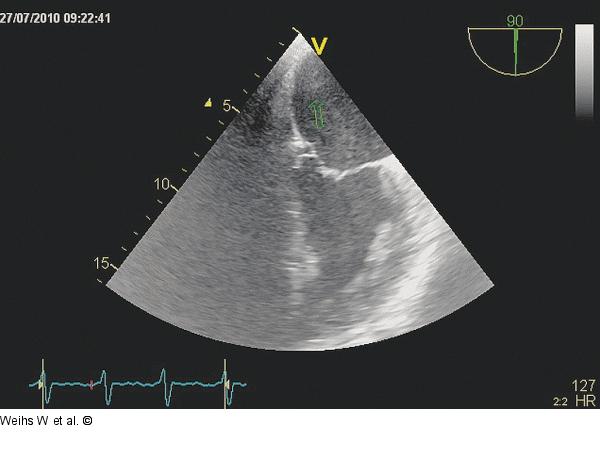

Abbildung 7: 2-Kammerblick 2-Kammerblick in der transösophagealen Untersuchung. Darstellung eines suspenkten Thrombus im Bereich des linksatrialen Daches (Pfeil). |

2-Kammerblick in der transösophagealen Untersuchung. Darstellung eines suspenkten Thrombus im Bereich des linksatrialen Daches (Pfeil). |